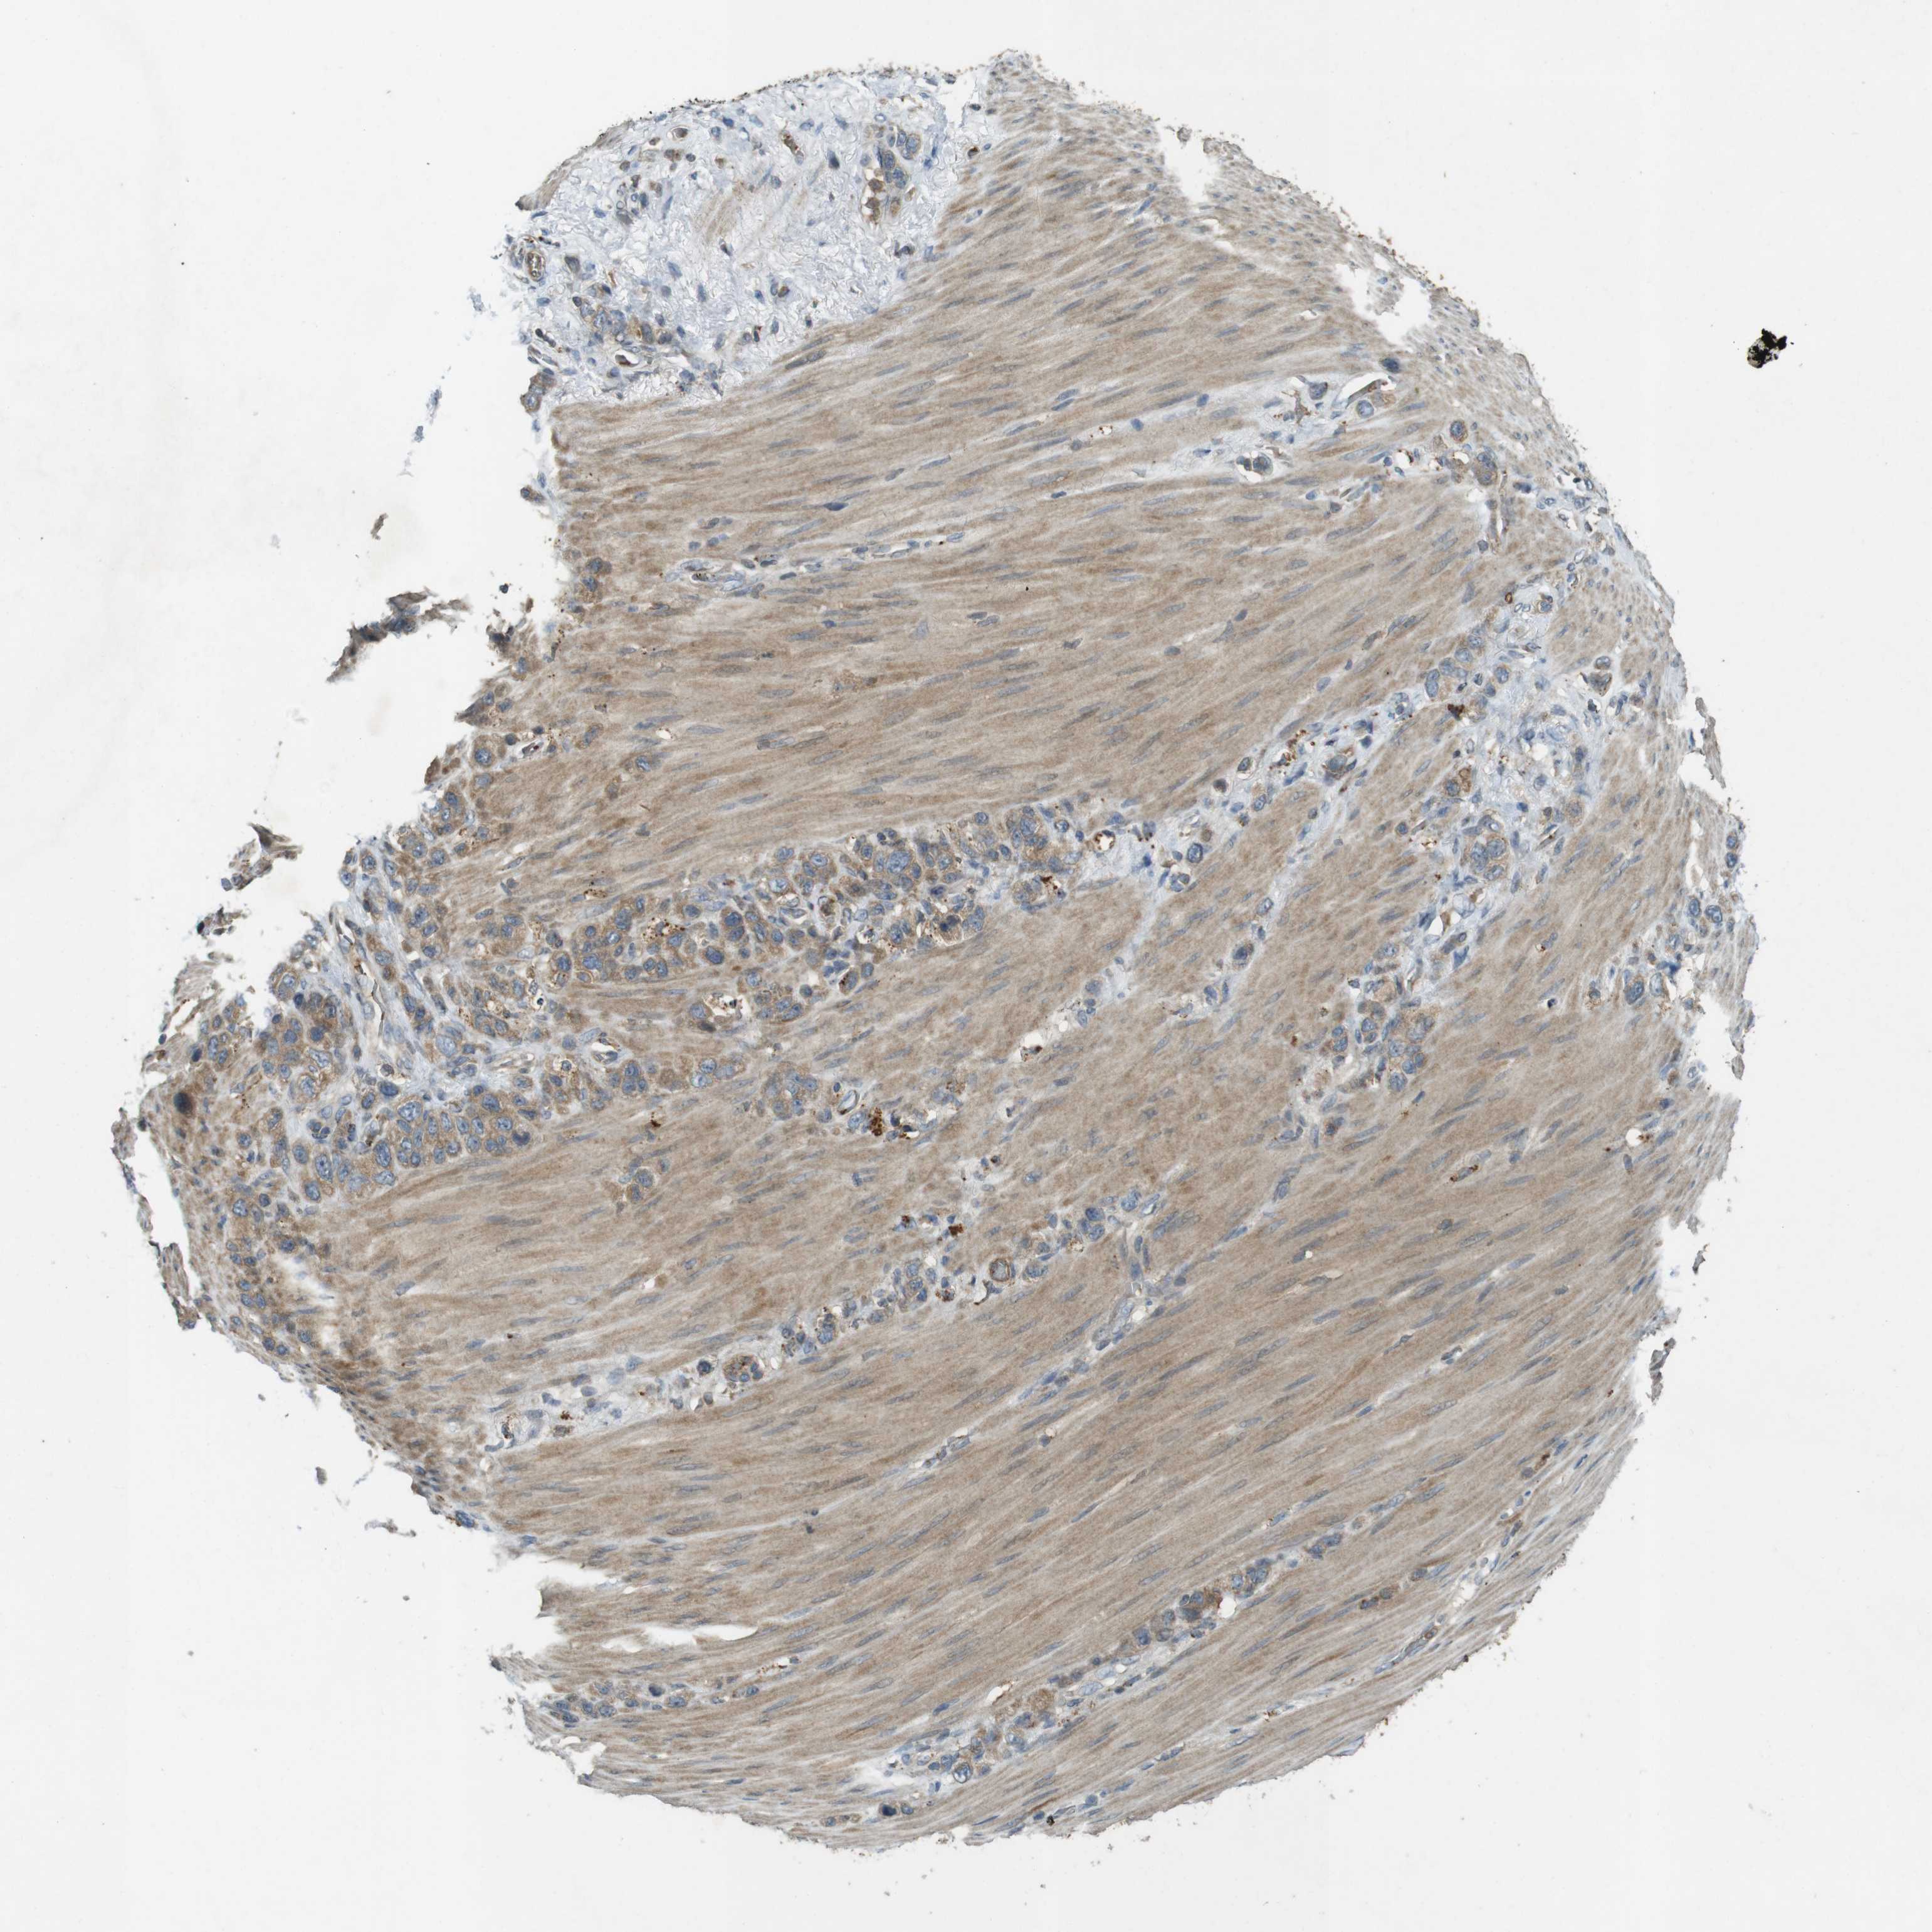

STOMACH CANCER - Protein expressioni

A mouse-over function shows sample information and annotation data. Click on an image to view it in a full screen mode. Samples can be filtered based on level of antibody staining by selecting one or several of the following categories: high, medium, low and not detected. The assay and annotation is described here.

Note that samples used for immunohistochemistry by the Human Protein Atlas do not correspond to samples in the TCGA dataset.

Antibody stainingi

Antibody staining in the annotated cell types in the current human tissue is reported as not detected, low, medium, or high, based on conventional immunohistochemistry profiling in selected tissues. This score is based on the combination of the staining intensity and fraction of stained cells.

Each image is clickable and will lead to virtual microscopy that enables deeper exploration of all samples and also displays staining intensity scores, fraction scores and subcellular localization as well as patient and tissue information for each sample.

Antibody HPA004835

Antibody HPA073497

Antibody CAB009321

Antibody CAB075747

Staining

High

Medium

Low

Not detected

Intensity

Strong

Moderate

Weak

Negative

Quantity

>75%

75%-25%

<25%

None

Location

Nuclear

Cytoplasmic/membranous

Cytoplasmic/membranous,nuclear

Adenocarcinoma, NOS

Adenocarcinoma, High grade